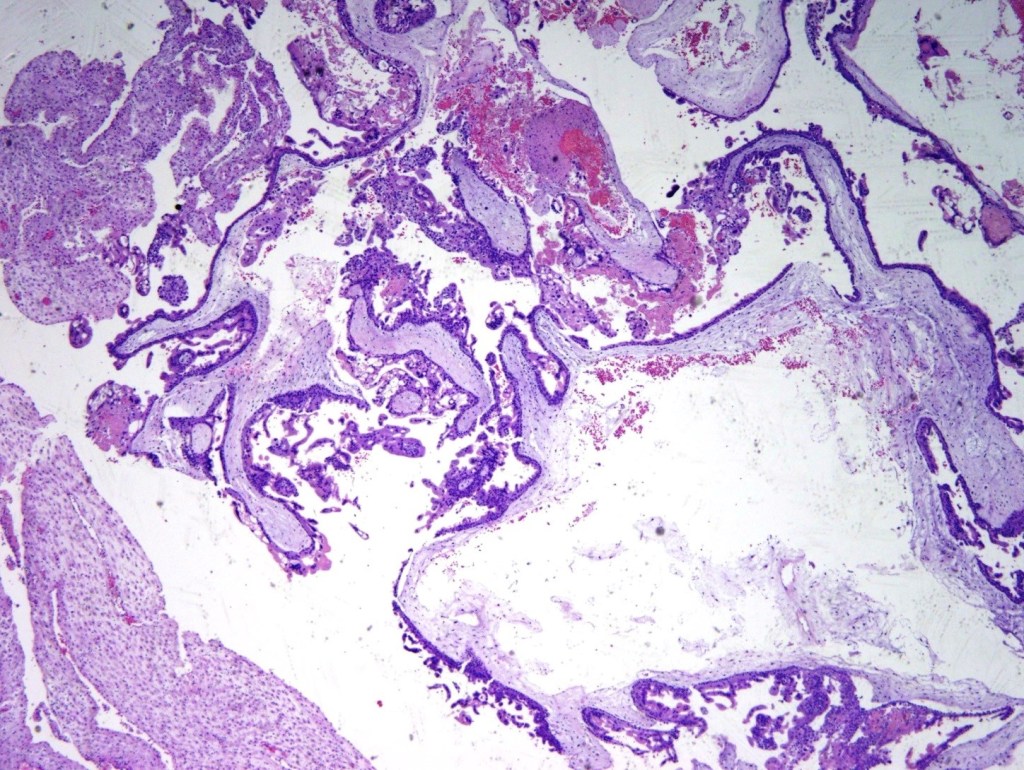

PARTIAL HYDATIDIFORM MOLES:

- The low-power view reveals a mix of small fibrotic villi and larger villi (figure 9).

- Some trophoblastic proliferation (in lace-like pattern) can be seen (figure 10).

- A limited number of cisterns are many times appreciated.

Differential diagnosis: very early complete hydatidiform mole or chromosomal abnormalities such as trisomies (figure 10).